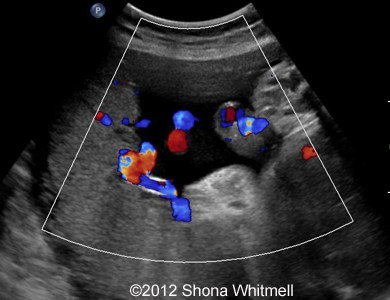

Figure 1: 3-vessel cord at the fetal end

Image-18

Image-17